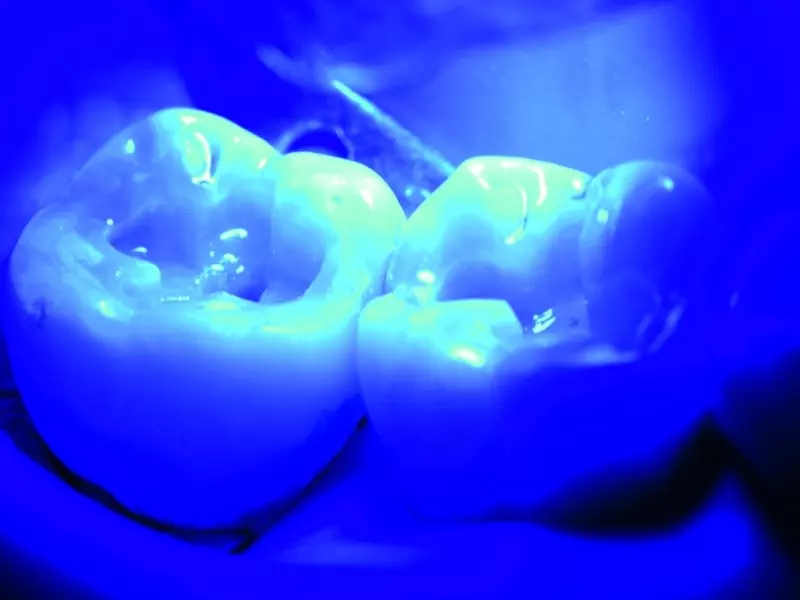

Wreszcie odbudowano kolejno pozostałe zęby, stosując tę samą procedurę co w przypadku zęba 36. (zdj. 16–31). Następnie wypolerowano wypełnienia silikonowymi gumkami pokrytymi diamentami, szczoteczkami, polerkami filcowymi i pastami polerskimi (zdj. 32 i 33).

Powstałe wypełnienia mają zadowalający wygląd i są satysfakcjonujące pod względem czynnościowym (zdj. 34 i 35).